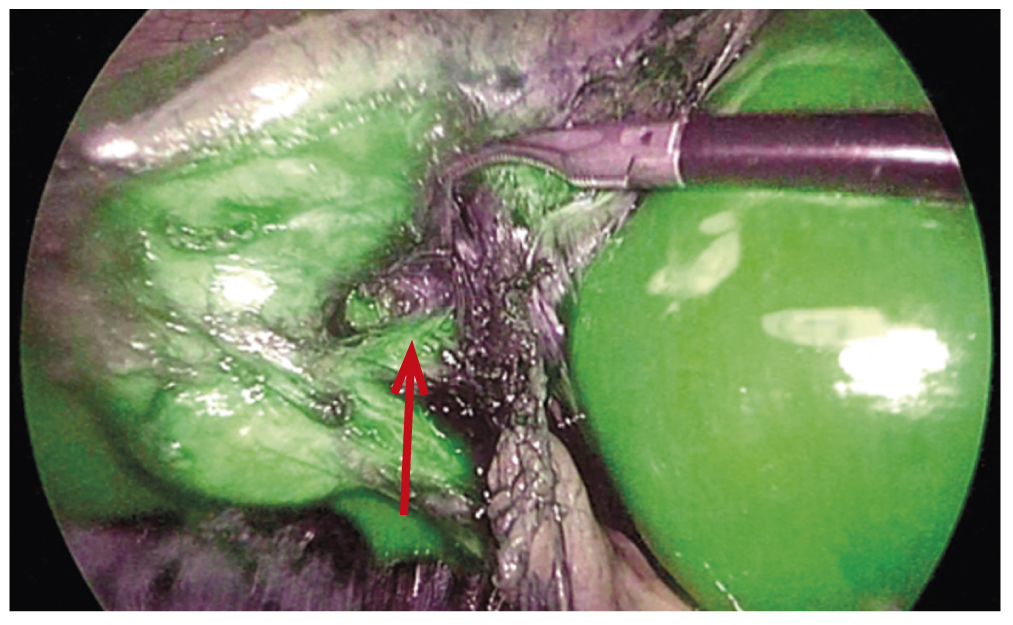

Based on the results of the research, in a group of 276 patients undergoing the laparoscopic cholecystectomy with ICG-fluorescent visualization of the extrahepatic bile ducts, no complications were observed. In 23 (8.3%) patients, the complications were successfully avoided by clear following the technique of critical view safety (CVS) and by using the intraoperative fluorescent ICG-cholangiography (examples provided in Fig. 1, 2).

Fig. 1. Mirizzi syndrome: tight fusion of the Hartmann pouch with the hepatic duct (arrow) due to inflammation (incipience of Mirizzi syndrome formation).